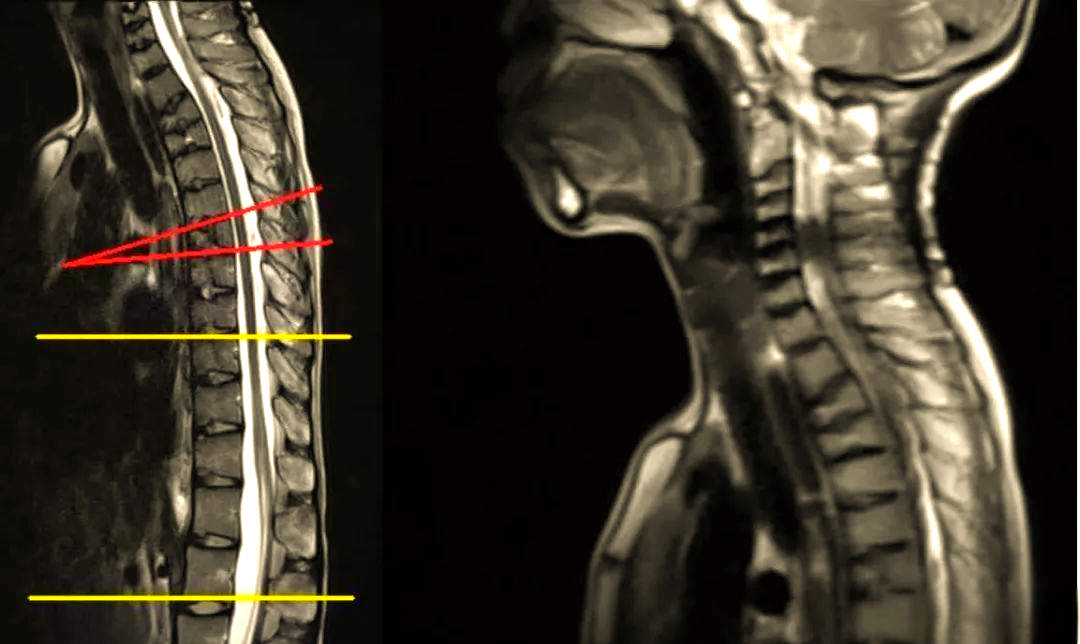

脊柱相关scheuermannsdisease休门氏病

图片尺寸640x383